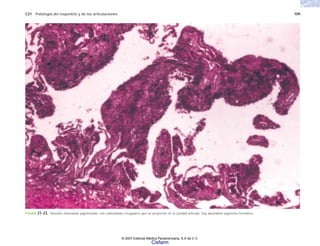

fenilalanina

H